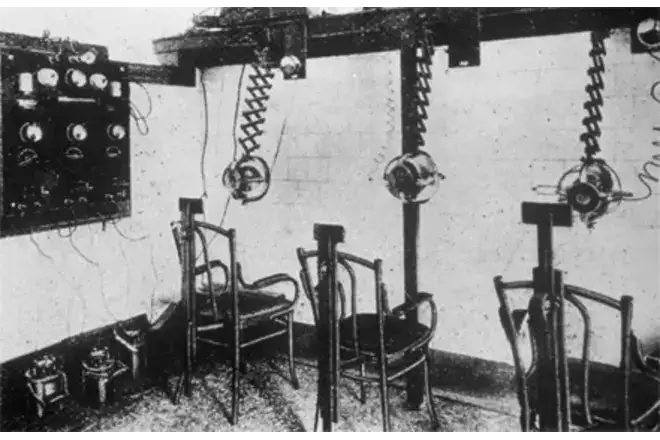

在谢巴的领导下,以色列的头癣治疗计划以惊人的规模展开。治疗的流程是这样的:首先,医生对儿童的头皮进行真菌检测,确认感染后将其送往放射科。在放射室里,儿童被安置在X光机前,头部被固定在一个特殊的位置。为了照射整个头皮,需要进行五次曝光——前额、后脑、两侧和头顶。每次曝光持续数秒至数十秒,辐射剂量约为350至400伦琴。这个剂量是当时公认的安全限值的七百倍至一千倍。